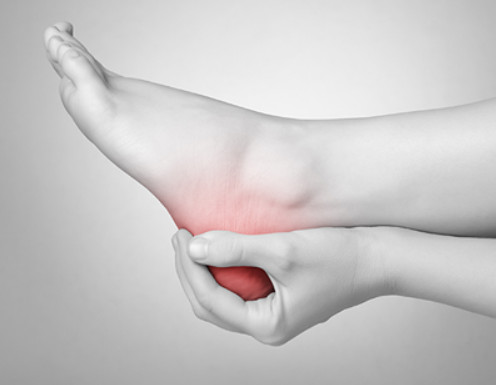

혹시 아침에 첫 발을 디딜 때 제일 아프다가 시간이 지나면 좋아지고, 오랫동안 활동하게 되면 발 뒤꿈치 안쪽 부분이 아픈 경험이 없으신가요? 이는 족저 근막염일 가능성이 높습니다. 오늘은 이러한 족저 근막염 치료법에 대해서 살펴보도록 하겠습니다.

족저근막염이란 발바닥 뒤꿈치에 염증이 생기면서 나타나는 발바닥 통증을 일컫습니다. 이는 남성보다 여성이 2배 정도 많이 발병된다고 하는데, 그 원인은 과도한 발의 스트레스나 운동으로 인해 발병된다고 합니다. 이 밖에 몸무게의 급격한 증가나 평발도 발병 확률을 높이는 원인이 됩니다.